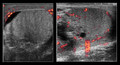

Decreased testicular power Doppler flow in the image on the left indicated torsion